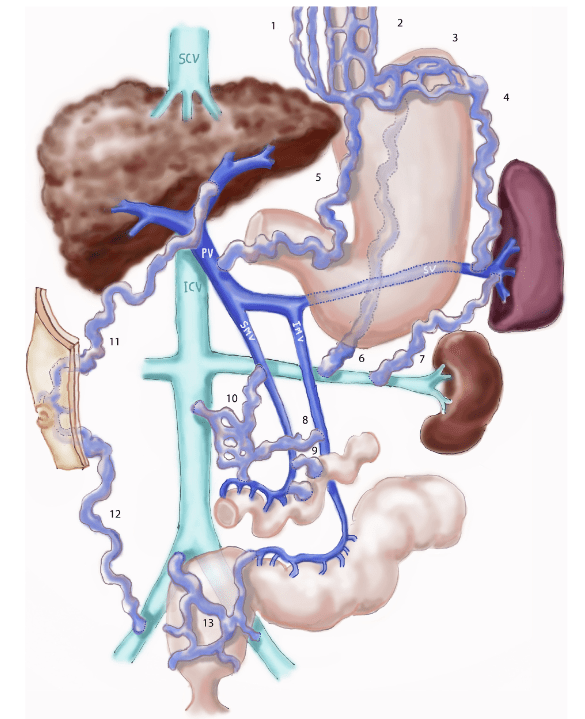

Para se ter uma ideia da importância do fígado no metabolismo basta observar como é a circulação do sangue: todo o sangue que sai do intestino, rico em nutrientes e toxinas, se junta em uma única veia, a veia porta, que distribui o sangue pelo fígado. Em relação à encefalopatia, a toxina mais importante é a amônia, que é produzida pelas bactérias intestinais.

No fígado normal, o sangue fui bem da veia porta até as veias centrais e de lá para as veias hepáticas e a circulação geral. À medida que uma doença (hepatite, lesão pelo álcool, etc.) evolui para a cirrose, o fluxo de sangue fica mais difícil tanto pela inflamação quanto pela presença de cicatrizes, aumentando a pressão na veia porta. Essa hipertensão portal leva a dilatação tanto da veia porta como das veias que levam a ela, causando aumento do baço (esplenomegalia), acúmulo de água no abdome (ascite), varizes esofágicas e, algumas vezes, uma ou mais pequenas veias que iam direto do intestino ou do baço para a circulação geral, causando um “curto circuito” (chamado “shunt portosistêmico) e levando o sangue repleto de neurotoxinas direto para o cérebro.